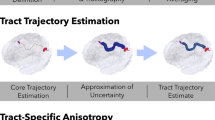

The key idea of our method (Fig. 1) is to do a segmentation of the principal eigenvector field into stable voxels having a minimal e1 variation (curvature). Thus, a voxel P is a member of the stable fiber mass, if there is a neighboring voxel Q such that e1‘s at P and Q point out to each other. Mathematically, it translates to the relation G(F(P)) = P, where with u = (1,1,1)

The method, thus, firstly generates the stable fiber mass and then segments it by coloring its voxels according to the following scheme. The vector joining P and Q has form (l,m,n), (l,m,n = −1,0,1) using which the voxel P is colored according to table. Typical segmented axial, sagittal, and coronal color maps were generated. Using these color maps, our method narrows down the ROIs selection to pointing out to a color segment inside a broader ROI through a single mouse click.

Diffusion tensor tractography.

Different fiber bundles are easily reconstructed by the segmented components using fiber assignment by continuous tracking algorithm (23). This reconstruction allowed us to identify the coordinates of specific WM tracts and to investigate the anatomy. DTI measures were calculated for the entire fiber and reported. FA threshold of 0.15 was used for fiber tracking.

Demonstration of methodology used for tract reconstruction from 7-y old healthy subject. (A) Sagittal CC and coronal SLF, ILF, CNG, and Fx stable fiber mass maps (first row) showing selection of planes for the reconstruction of respective right tract. (B) Demonstration of methodology used for motor (first row) and sensory tract (second row) reconstruction.